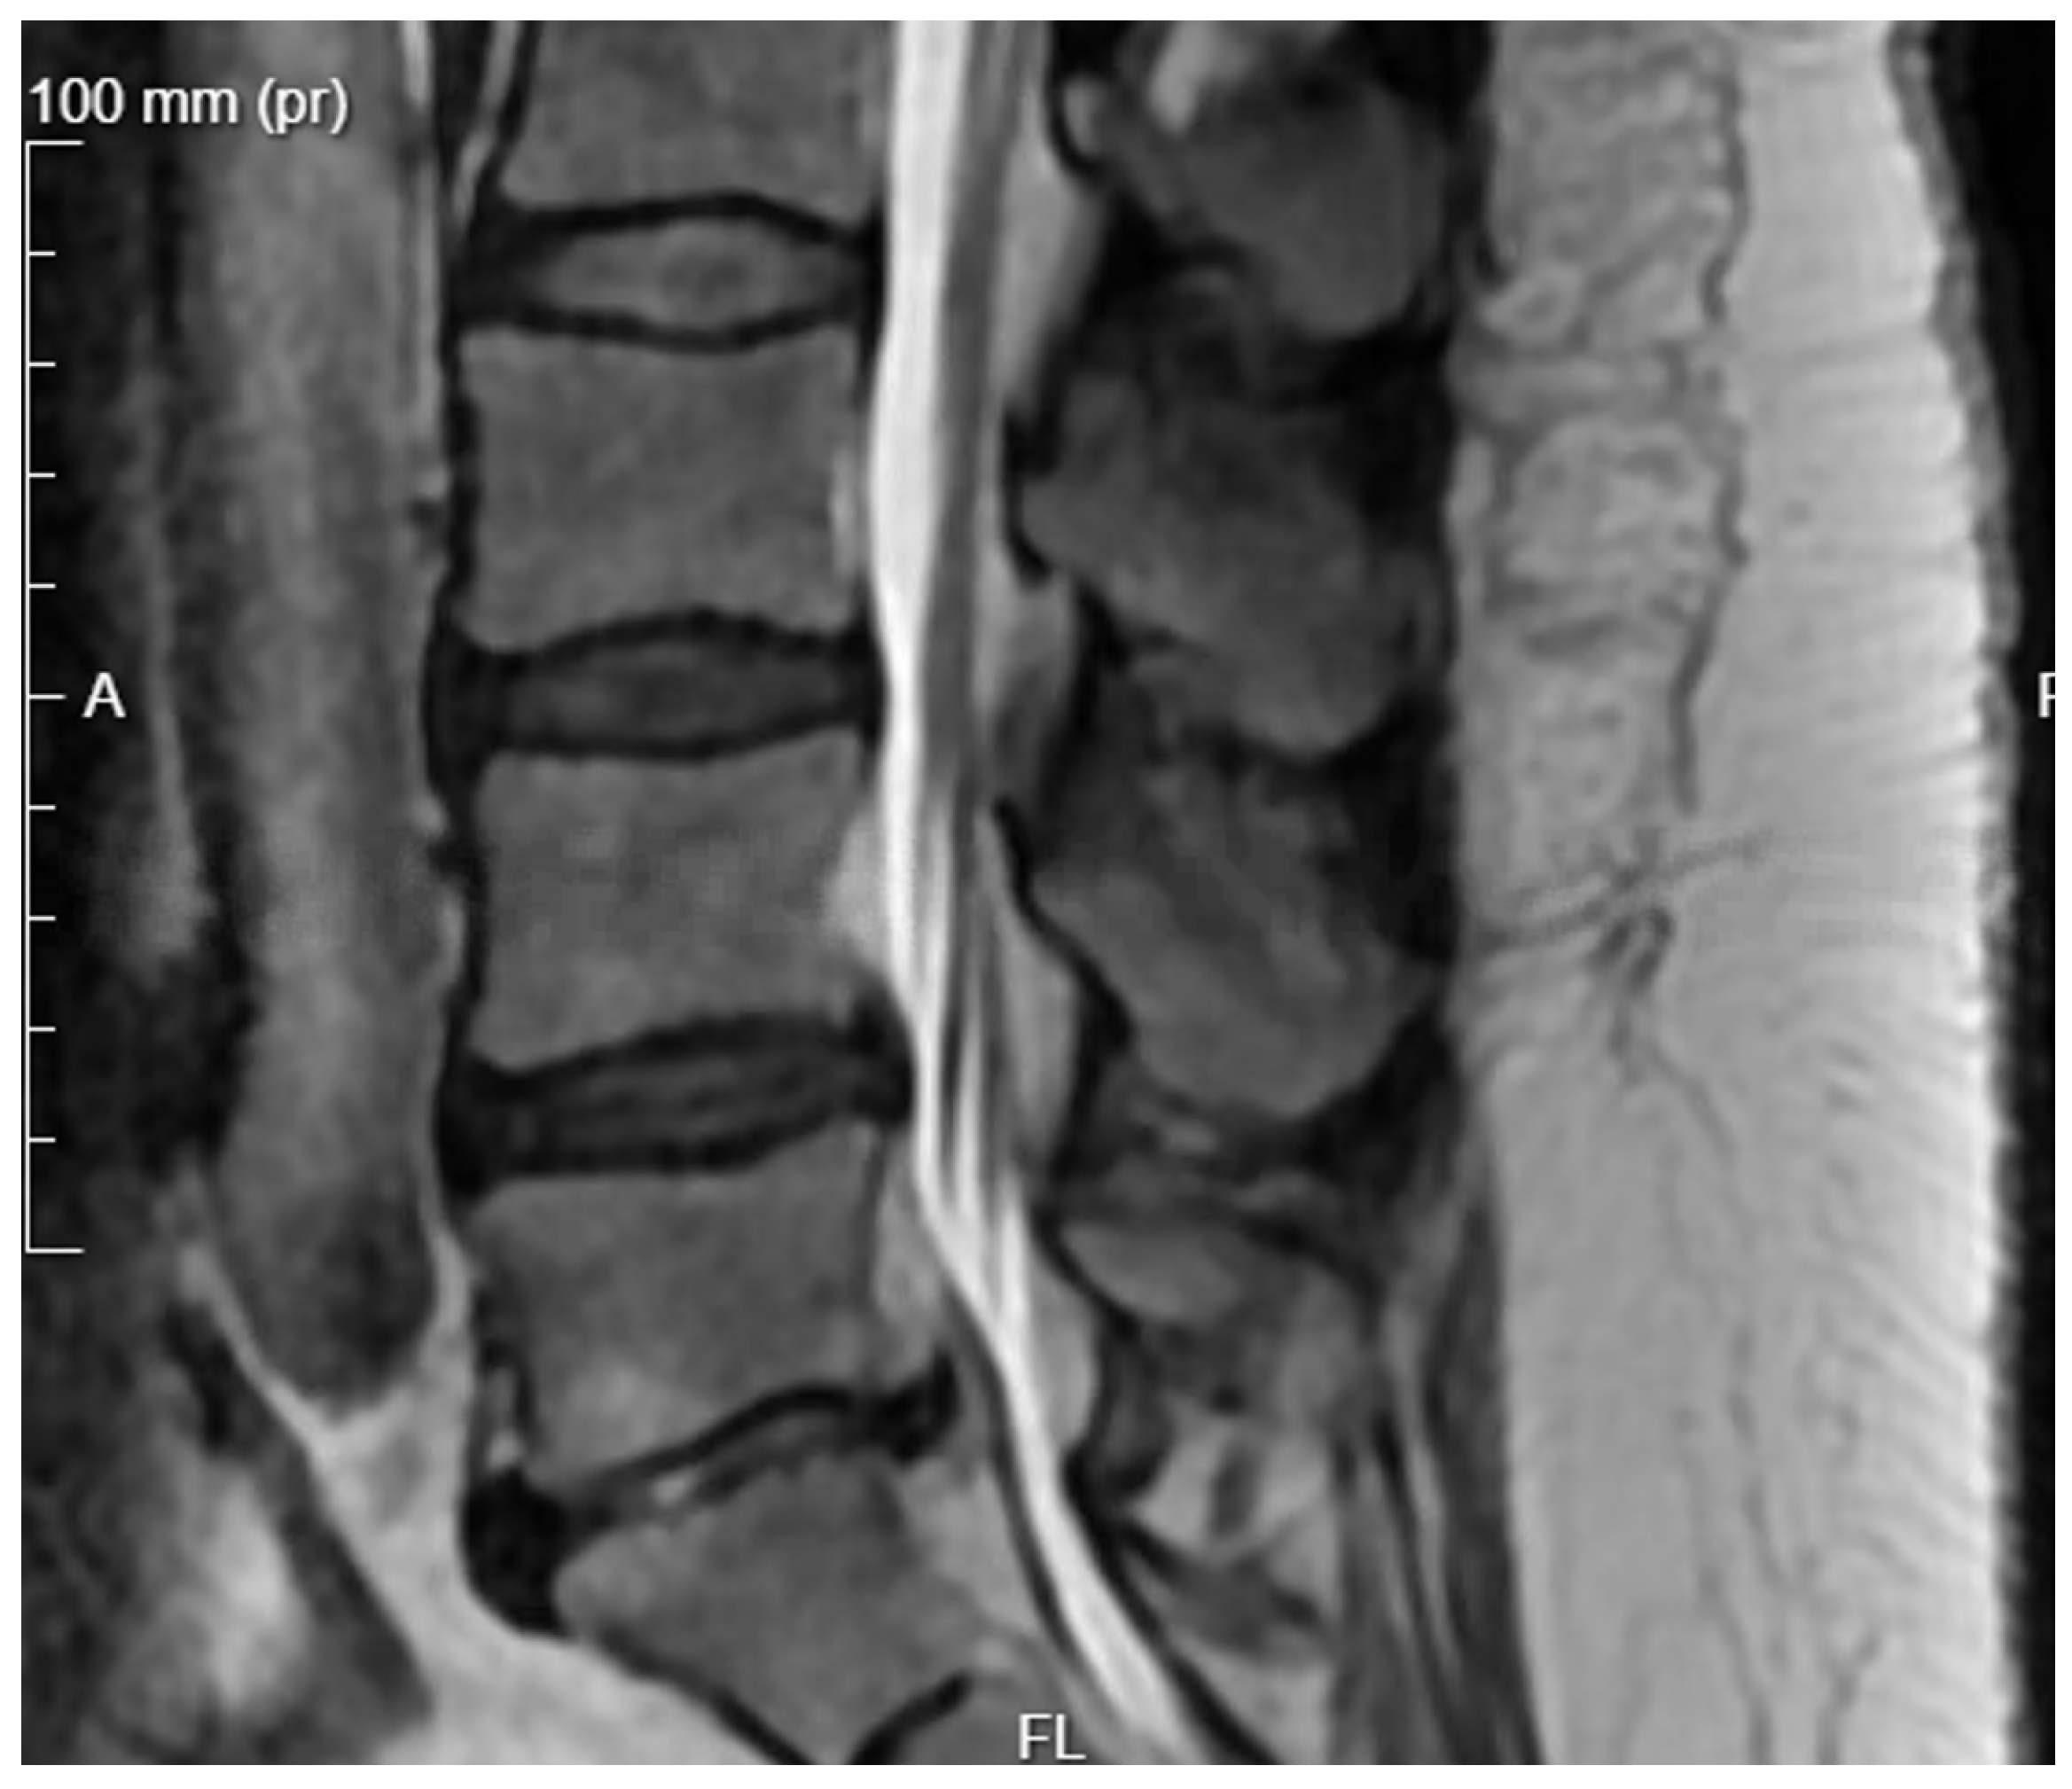

Diagnostic Evaluation: Cultures taken were sterile, and the patient was empirically treated with antibiotics until inflammatory markers decreased. He was discharged in good condition without pain. Six months later, the surgical site re-opened with purulent discharge seeping out. A new culture was taken, which returned sterile. Laboratory tests showed an increase in inflammatory markers, and the patient periodically experienced fever. CT scans showed the stabilization was in the correct position but without signs of bone fusion, and MR images showed inflammatory masses within the spinal canal (Figure 9 and Figure 10).

Figure 10. Pre-operative T2 sagittal MRI.